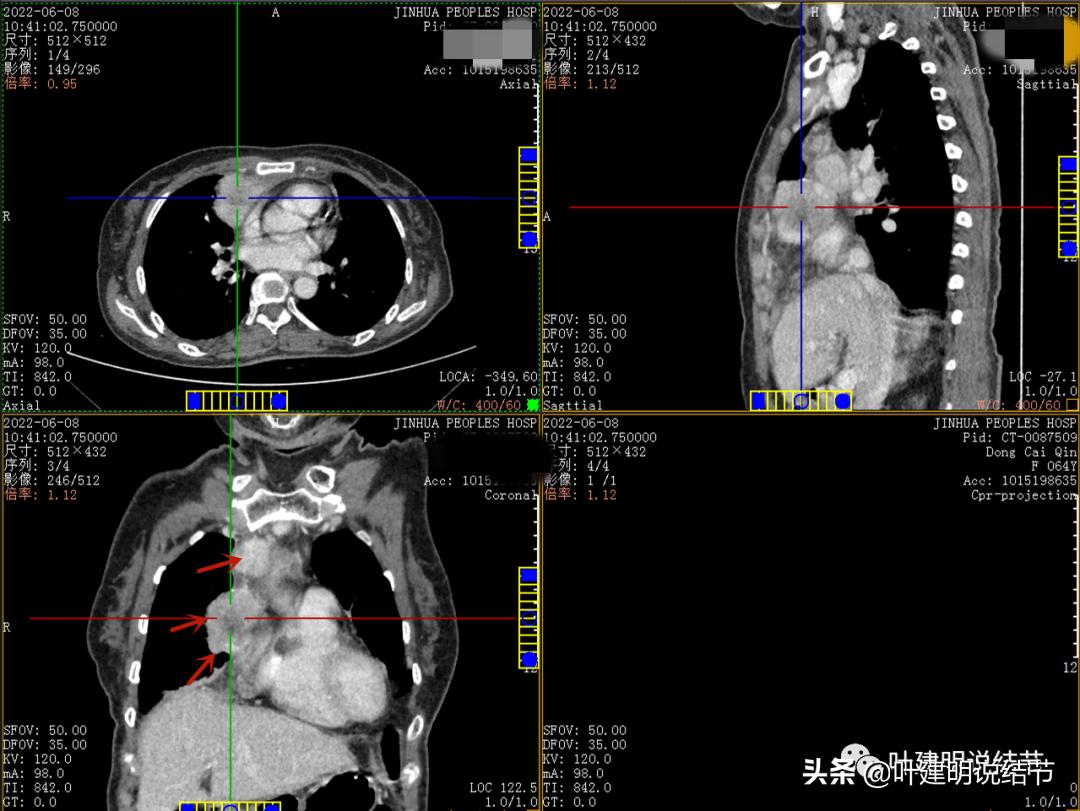

粉色箭头示淋巴结可能

绿色箭头示近膈面处,心脏边病灶

此灶与主病灶不是完全相连的

病灶最大横断面水平,在冠状位上显示病灶多个中心似的,从上到下纵隔都有

病灶之间似不相连的,矢状位上见从上到下延续的